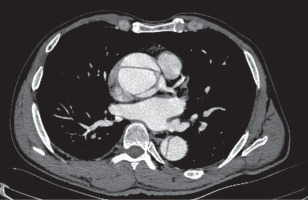

The patients’ baseline demographic characteristics are summarized in Table I. Forty-six patients who underwent emergency surgical repair for ATAAD between January 2021 and April 2024 were retrospectively evaluated. ATAAD was defined as an aortic dissection (AD) detected within 14 days after the onset of symptoms. The anatomy of AD was classified according to the DeBakey classification [8]. Prior to the procedures, all patients underwent transthoracic echocardiography (TTE) performed by expert cardiologists. The radiologist and cardiovascular surgery team then performed computed tomography angiography (CTA), thoroughly examined the images, and verified the findings intraoperatively (Figures 1, 2). At presentation, dissection extent was DeBakey type I in 37 (80.4%) and type II in 9 (19.6%). The patients were grouped as those with right AXA cannulation (group 1, n = 18) and IA cannulation (group 2, n = 28). The groups were compared based on preoperative, intraoperative, and postoperative data. The GERAADA score was calculated individually for each patient using a web-based tool by a cardiovascular surgeon who was blind to the study [9]. All procedures were carried out by different surgeons using similar techniques.

The choice between AXA and IA cannulation was ultimately left to the judgment of the operating surgeon. IA was not used for cannulation in the presence of atherosclerosis, aneurysmal dilatation of the IA, small IA diameter, or extension of ATAAD to the IA.